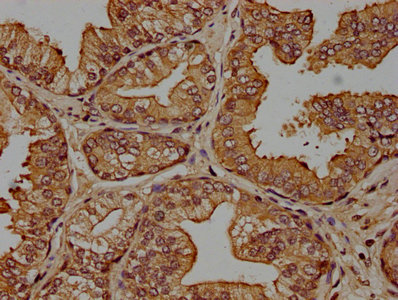

IHC image of CSB-PA005963OA01HU diluted at 1:100 and staining in paraffin-embedded human prostate cancer performed on a Leica BondTM system. After dewaxing and hydration, antigen retrieval was mediated by high pressure in a citrate buffer (pH 6.0). Section was blocked with 10% normal goat serum 30min at RT. Then primary antibody (1% BSA) was incubated at 4°C overnight. The primary is detected by a biotinylated secondary antibody and visualized using an HRP conjugated SP system.